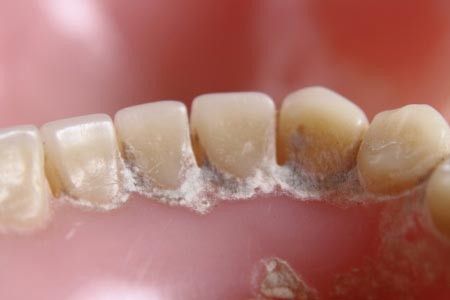

Banyak orang yang mengabaikan keberadaan karang gigi (dental calculus) di dalam mulut, karena dianggap sebagai sesuatu yang tidak membahayakan kesehatan tubuh. Padahal, karang gigi merupakan faktor utama terjadinya peradangan jaringan pendukung gigi (jaringan periodontal), yang disebut periodontitis.

Permukaan karang gigi yang kasar dan berpori menjadi tempat yang ideal bagi pertumbuhan bakteri dalam rongga mulut dan bertindak sebagai wadah yang menampung bagi komponen produk bakteri yang bersifat toksik bagi jaringan lunak mulut.